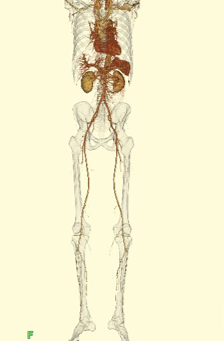

当クリニックでは、クリニックとしては珍しく、造影検査も行っています。主に心臓(冠動脈)や大動脈などの血管の検査が多い傾向です。様々な検査目的を満たすために、撮影方法や造影剤注入法、画像処理などを工夫し、より良い画像を提供しています。